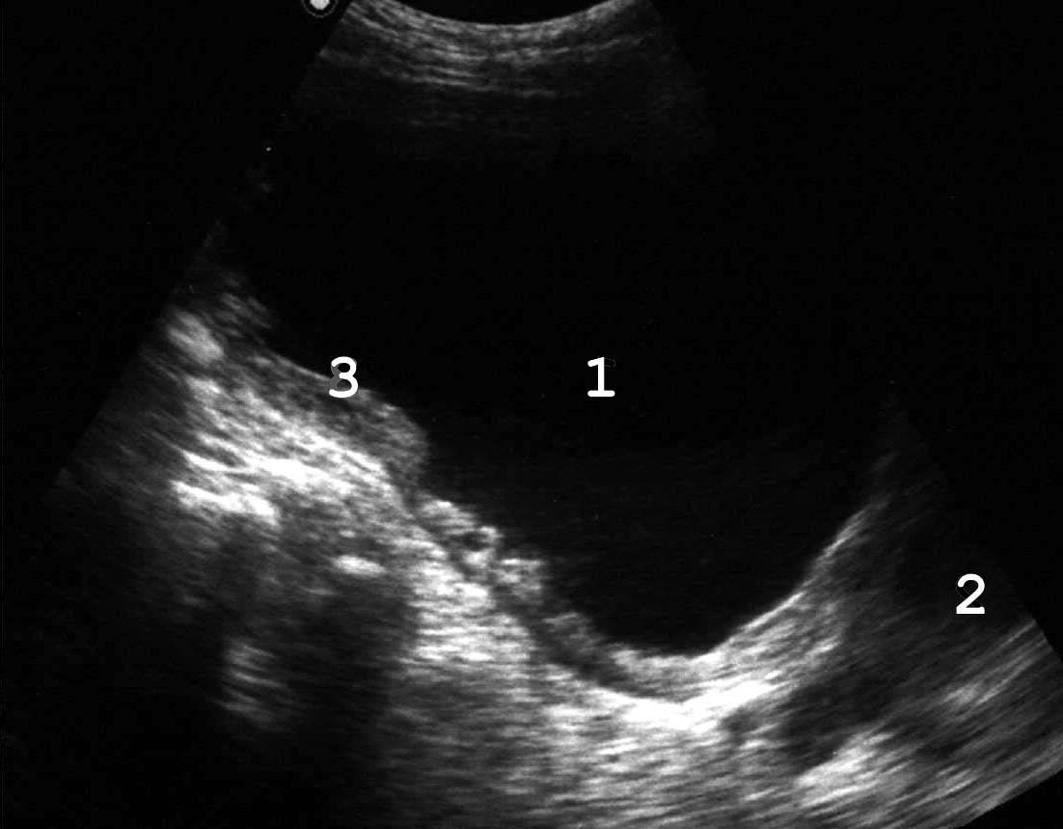

Рис. 11. Инфильтрация задней стенки мочевого пузыря при распространенной злокачественной опухоли прямой кишки: 1 − мочевой пузырь, 2 − инфильтрированная задняя стенка; 3 − опухолевый конгломерат малого таза. (Продольное сканирова-ние, конвексный датчик 5 МГц, “Logiq-500”).